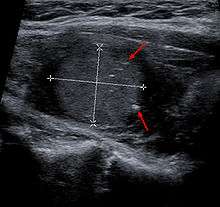

Medullary thyroid carcinoma may also produce a thyroid nodule and enlarged cervical lymph nodes.[3]